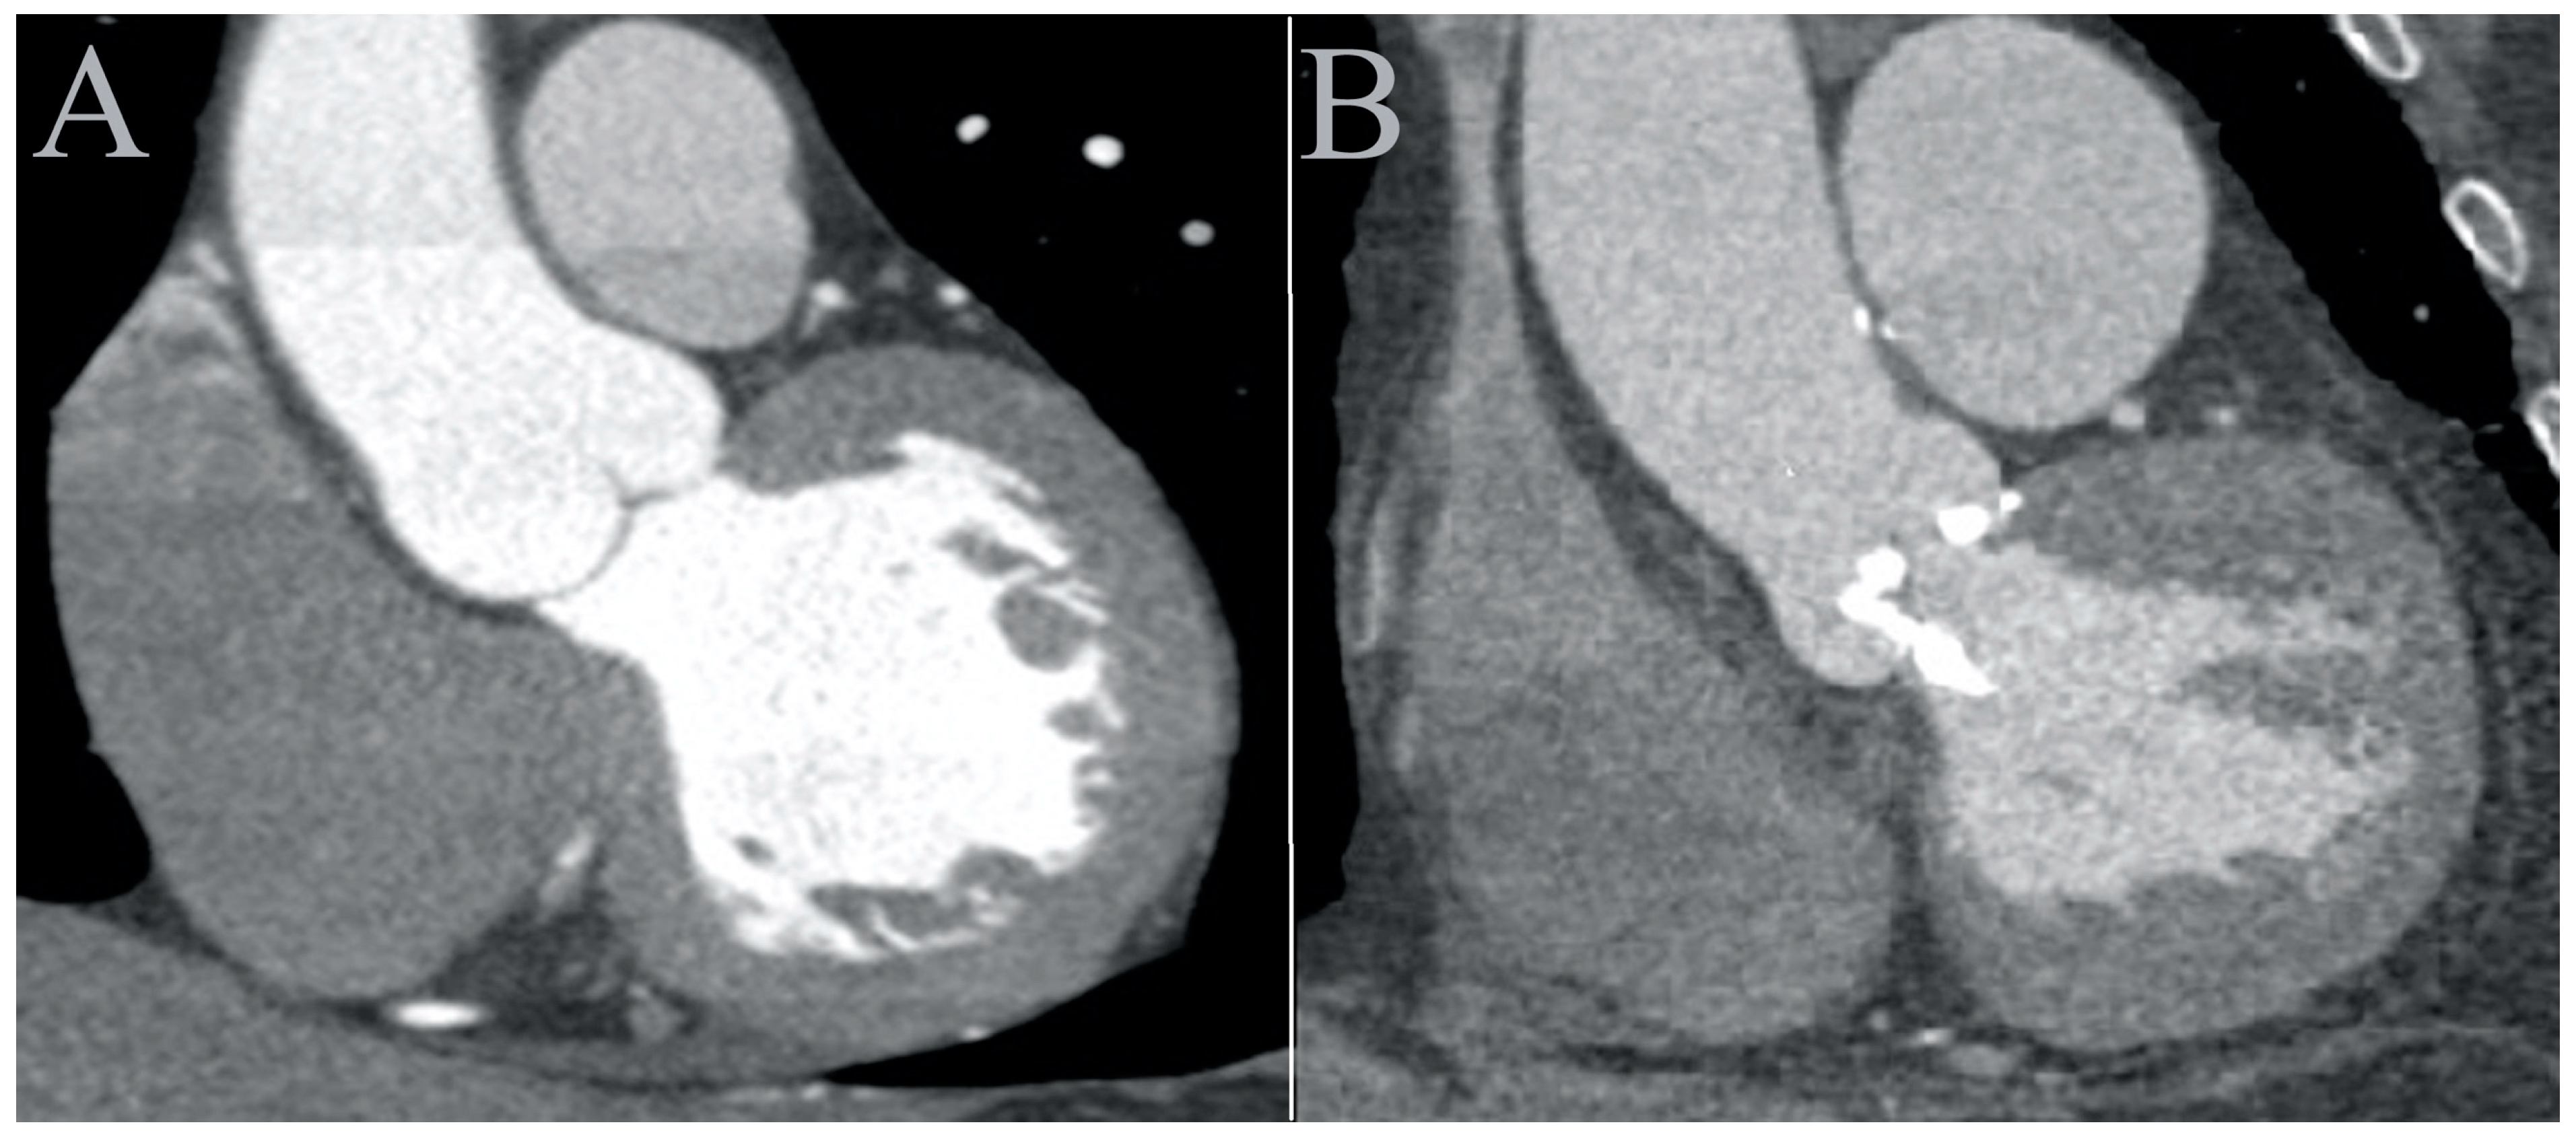

2. Methods

- Twelve distinct regions in 3D reconstruction mode: 4–5 mm above the opening of the aortic valve (OAV); at the junction of the leaflets and the fibrotic annulus (left, AL; right, AR; and non-coronary, AN); the mid-level of the sinus of Valsalva at the most lateral (Valsalva lateral left, VLL; Valsalva lateral right, VLR; and Valsalva lateral non-coronary, VLN) and at the mid-point (Valsalva center left, VCL; Valsalva center right, VCR; and Valsalva center non-coronary, VCN); and in the midline of the sinotubular junction (STJ) and 4 cm from the SJT (Figure 2). The region of interest was 3–5 mm2. Patients with a high grade of the beam-hardening effect due to severe calcification limiting the evaluation were excluded.

- Right and left ventricular outflow tract (RVOT/LVOT): 2–4 mm below the pulmonary and aortic valve in the centerline of the outflow tracts, respectively.